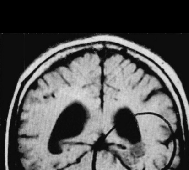

脑海绵状血管瘤无症状或者偶然发现,需要手术吗?脑海绵状血管瘤常会因非特异性或无关症状而做影像学检查时被发现(图1)。对于无症状的脑干海绵状血管瘤和单次发作并没有导致严...